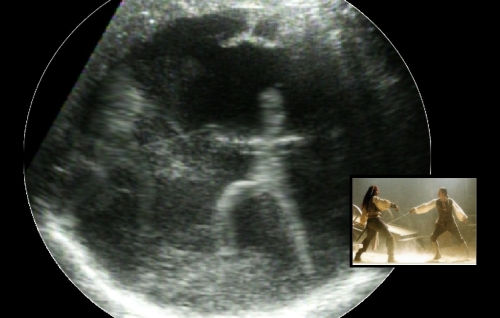

건국대병원에서 초음파 촬영 중 펜싱 경기를 떠올리게 토토사이트 테이블 이색적인 사진이 찍혀 눈길을 끌고 있다.

이 사진은 복부 초음파 촬영 중 간에서 발견된 큰 물혹 내의 출혈 자국이 찍힌 것으로, 펜싱 경기를 벌이는 선수들의 모습과 흡사하다.

특히 복부 가운데 위치한 출혈 흔적은 머리와 팔다리를 완벽하게 갖춘 사람의 형상을 하고 있으며, ‘x’자로 엇갈린 펜싱 칼의 형태도 비교적 뚜렷하게 식별된다.

이 사진의 제목은 ‘A master fencer(검술의 대가)’. 건국대병원 글로컬 소화기병센터장 심찬섭 교수가 촬영했으며, 2011년 대한초음파의학회 초음파영상 공모전에서 대상을 수상했다.